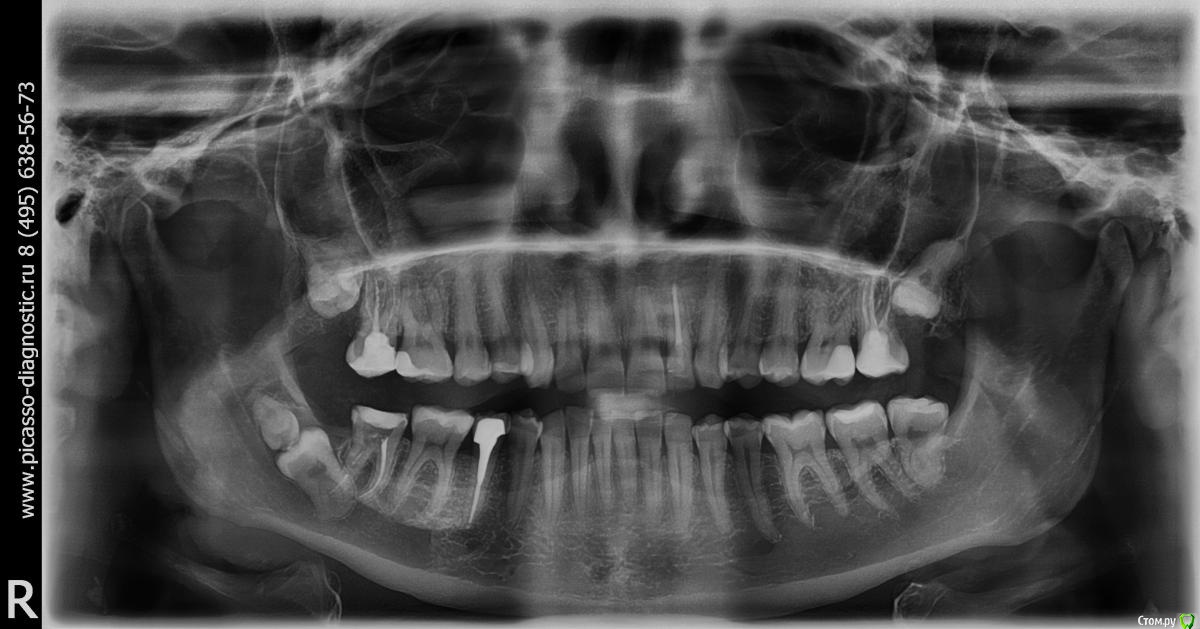

Kitten Опубликовано 20 декабря, 2014 Автор Поделиться Опубликовано 20 декабря, 2014 Я сделала ОПТГ и КТ. Ссылка на КТ ниже. Для тех, у кого нет возможности скачать файл полностью, приложила скриншоты. Жду ваши рекомендации. https://yadi.sk/d/3-GC2npldVBv4 Ссылка на комментарий

red_butler Опубликовано 13 декабря, 2014 Поделиться Опубликовано 13 декабря, 2014 у Вас там два зуба, делайте Кт и ищите грамотного хирурга и удаляйте оба до протезирования седьмого. Случай интересный 4 Ссылка на комментарий

Зубоволок 36 Опубликовано 13 декабря, 2014 Поделиться Опубликовано 13 декабря, 2014 у Вас там два зуба, делайте Кт и ищите грамотного хирурга и удаляйте оба до протезирования седьмого. Случай интересный Действительно похоже на то что и девятка имеется. Ссылка на комментарий

Kitten Опубликовано 13 декабря, 2014 Поделиться Опубликовано 13 декабря, 2014 (изменено) Добрый день, уважаемые специалисты Хочу с Вами проконсультироваться по сложному вопросу, за который не стали браться в платной клинике. После лечения глубокого кариеса зуба 4-7 остались две тонкие стенки, и я решила перейти к его протезированию. Перед установкой металлической вкладки сделали снимок, и оказалось, что зуб мудрости (или 8-ой зуб) лежит вертикально и цепляется корнями за семерку (снимок прилагается). А еще над семеркой есть "капюшон" (возможно, это тоже важная информация).8-ой зуб меня, в принципе, не беспокоит, десна не воспалена. Только иногда, когда думаю о нем, он как будто немножко ноет и "прорезаться" хочет. Хотя это мой мозг, возможно :-)Ортопед сказал, что без согласования хирурга протезировать зуб не будет, а местный хирург браться за мой случай не захотел, как я уже сказала. Посоветуйте, пожалуйста, что делать с восьмеркой: переходить к протезированию 7 зуба и не думать о нем или все-таки удалить. Если подскажите, куда можно обратиться по этому вопросу, буду признательна. Спасибо! Изменено 13 декабря, 2014 пользователем Kitten Ссылка на комментарий